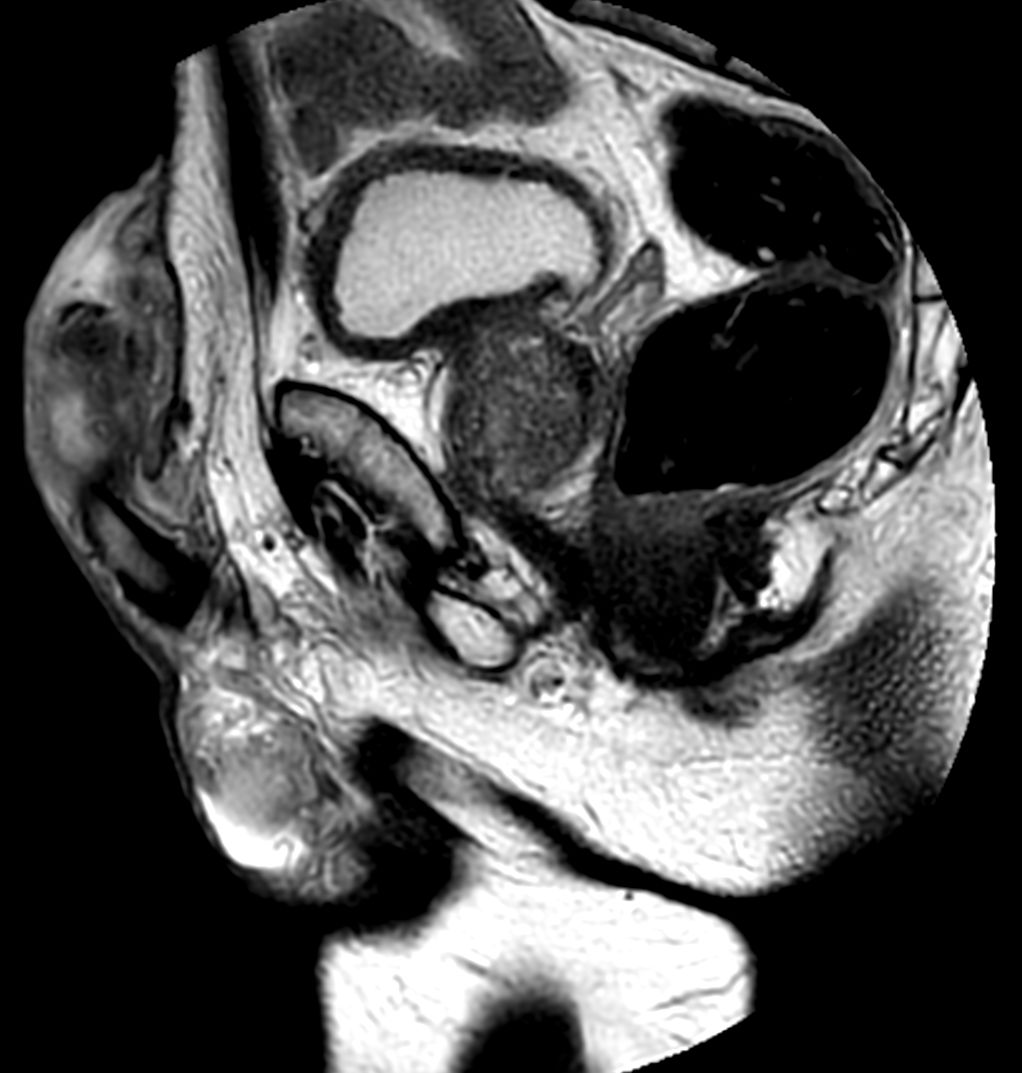

Patient with a penile carcinoma. ExamCard includes Compressed SENSE to shorten exam time, diffusion to achieve high contrast between background and lesions, and MultiVane XD for motion-free imaging in short scan time.

T2w TSE FatSat Compressed SENSE